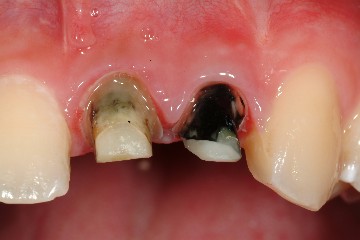

圖十八、十九為技師所完成的全瓷冠成品,氧化鋁全瓷冠有輕微透光性,可將牙齒的金屬釘柱遮光,但色澤與自然牙齒相仿,是牙科2000年後的最新科技發展。圖二十為裝牙齒前的情況,經試戴、調整、及黏著後,過了一週,病患回診所的結果(圖二十一、圖二十二),經過全瓷冠的修復,患者得到滿意的結果,可以再度露出自信且迷人的笑容了。

圖二十 |